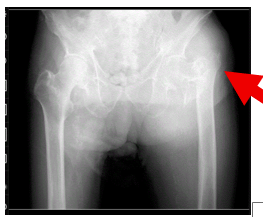

【在宅でみる大腿骨近位部骨折】手術できない高齢者をどう支えるか

高齢化の進行に伴い、大腿骨近位部骨折(だいたいこつきんいぶこっせつ)を受傷される高齢者が年々増加しています。 通常であれば手術が推奨される骨折ですが、 全身状態が悪い すでに歩行困難 認知症が進行し、手術後の脱臼肢位保持が難しい といった理由から、「 手術適応なし...

【在宅医療の現場から】高齢者の骨折予防とビタミンD製剤の注意点

高齢者が寝たきりになる原因のひとつに 骨折 があります。特に注意が必要なのは、 大腿骨頸部骨折(足の付け根の骨折) 脊椎の圧迫骨折(腰椎など) です。 これらの骨折、とくに大腿骨頸部骨折は**保存的治療(手術をしない選択肢)**が難しく、多くの場合、 手術 → ベッド上安静...